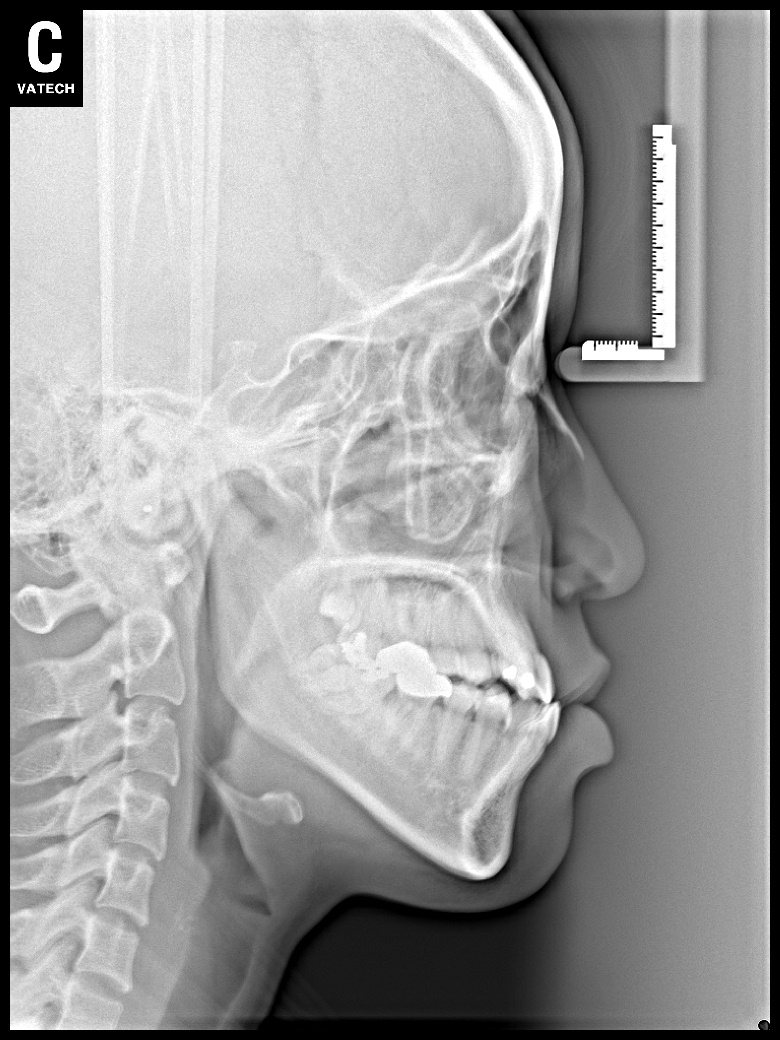

치료 후 사진입니다.